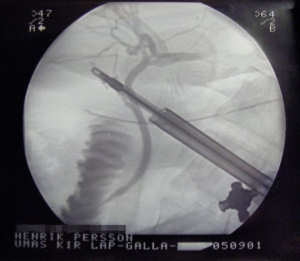

X-ray taken during a laprasopic cholecystectomy